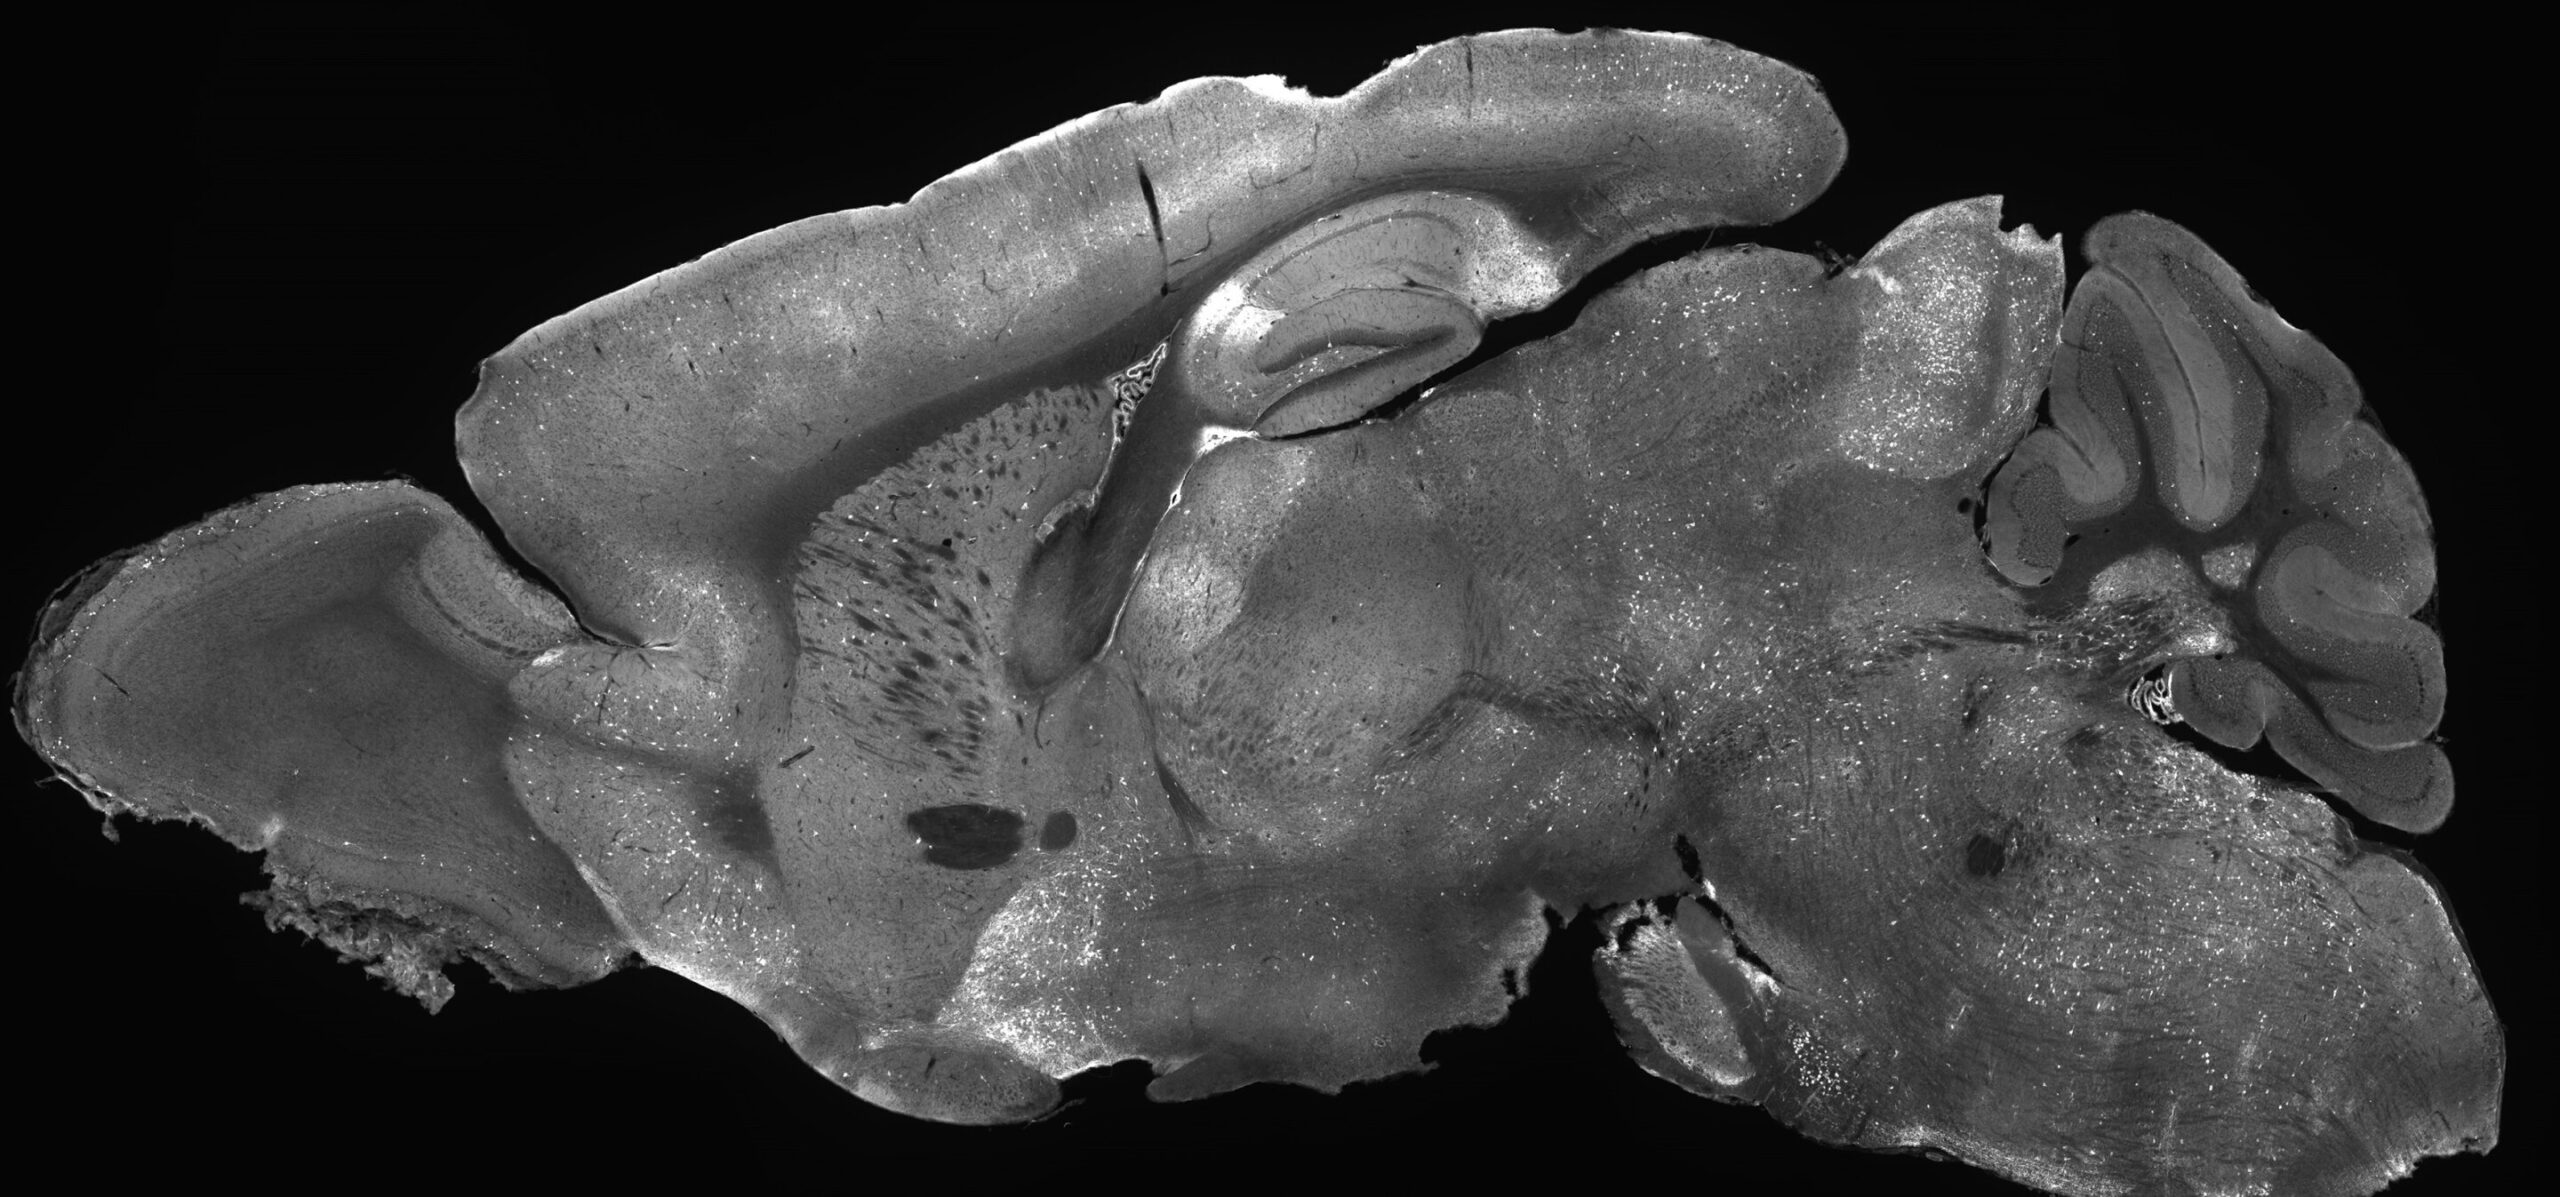

Imagem do cérebro de camundongo brilhando com terapia experimental de suplementação genética, destacando como o AAV oferece tratamento em todo o cérebro. Crédito: Instituto Allen/Andrew Clark

As descobertas, recentemente publicado no diário Terapia Molecularrepresentam a primeira terapia de suplementação genética bem-sucedida para SRDs na qual um vírus adeno associado (AAV) foi usado para entregar uma cópia funcional do gene SYNGAP1 nas células cerebrais. Os AAVs são vírus não replicantes que agem como caminhões de entrega que transportam carga terapêutica, neste caso o gene SYNGAP1, para as células que dela necessitam.